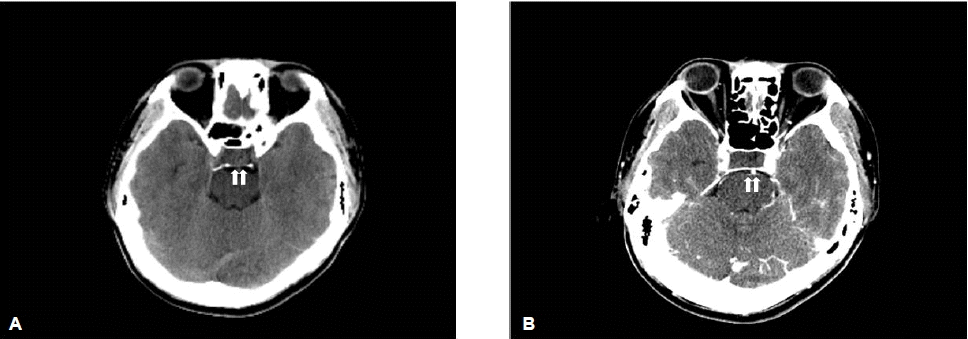

영상학적 소견: 전산화 뇌 단층 촬영에서 뇌하수체에 1.3 cm의 뇌하수체 우연종 외에 특이소견은 없었다(그림 1),

Figure 1.

Axial non-enhanced (A) and enhanced (B) CT images show an isodense pituitary adenoma (indicated by the white arrow).